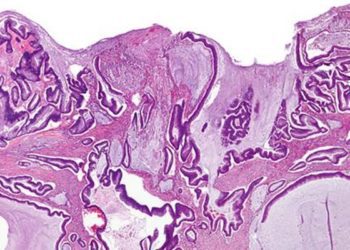

Study Rundown: Colorectal cancer (CRC) is the second leading cause of cancer death worldwide. Roughly half of patients with CRC eventually develop liver metastases, which are increasingly responsive to curative resection thanks to advances in diagnostics, oncologic treatment, and surgical techniques. Laparoscopic liver surgery is minimally invasive and has been shown in numerous retrospective studies as well as the randomized controlled OSLO-COMET trial to improve short-term outcomes relative to open surgery, but the long-term effects of each approach were unclear. In this OSLO-COMET extension study, no differences in recurrence-free survival or overall survival were detected between patients in the laparoscopic group and patients in the open group at 5 years. Median recurrence-free survival was also similar between groups. However, given the limited sample size, the possibility of small to moderate differences in survival in either direction could not be excluded. This study was conducted at a single high-volume surgical center, which minimized case-to-case variation, but this design also limited generalizability to other, non-expert settings. Future multicenter randomized controlled trials may reveal more insight regarding noninferiority and other specific secondary endpoints.

In-Depth [randomized controlled trial]: Between February 2012 and February 2016, 280 patients with colorectal liver metastases were assigned using block randomization to receive either laparoscopic or open parenchyma-sparing liver resection (fewer than 3 consecutive liver segments). Patients who required formal hemihepatectomy, vessel or bile duct reconstruction, or ablation were excluded. Survival analysis was performed in January 2020, and median overall survival was 80 months (95% CI, 63 to 97 months) in the laparoscopic surgery group and 70 months (95% CI, 48 to 92 months) in the open surgery group (hazard ratio [HR], 0.93; 95% CI, 0.67 to 1.30). Overall survival rates for 1, 3, and 5 years were 94%, 71%, and 54%, respectively, in the laparoscopic group and 93%, 71%, and 55% in the open group (between-group difference at 5 years, 0.5 percentage point; 95% CI, −11.3 to 12.3 percentage points). Median recurrence-free survival was 17 months (95% CI, 10 to 23 months) in the laparoscopic group and 16 months (95% CI, 8 to 24 months) in the open group (HR, 1.09; 95% CI, 0.80 to 1.49; P = 0.57); the 5-year recurrence-free survival rate was slightly higher in the open surgery group (36% vs. 30%; 95% CI, −6.7 to 18.7 percentage points). A total of 60 patients required repeat surgery for recurrent liver metastases.